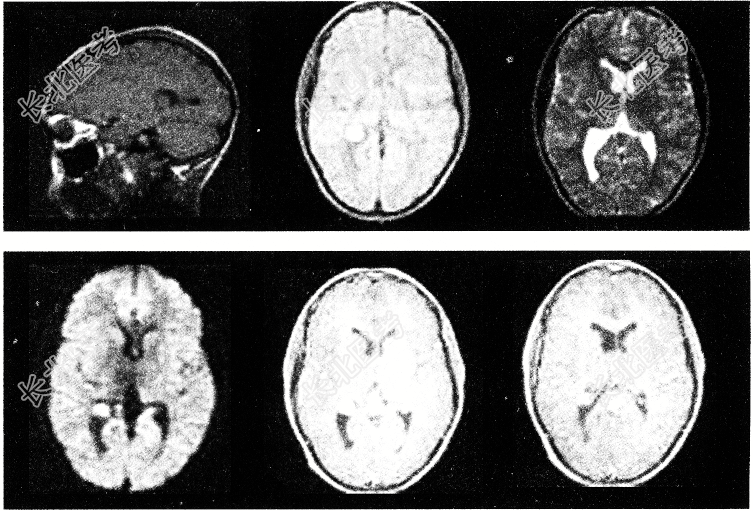

- 单项选择题有关脑室内脑膜瘤(如图所示),以下哪项说法不恰当

A、侧脑室内脑膜瘤多位于侧脑室三角部

B、三、四脑室内脑膜瘤可引起梗阻性脑积水

C、起始于脉络丛

D、脑血管造影显示侧脑室内脑膜瘤供血动脉多为大脑中动脉

E、临床常见头痛、视盘水肿